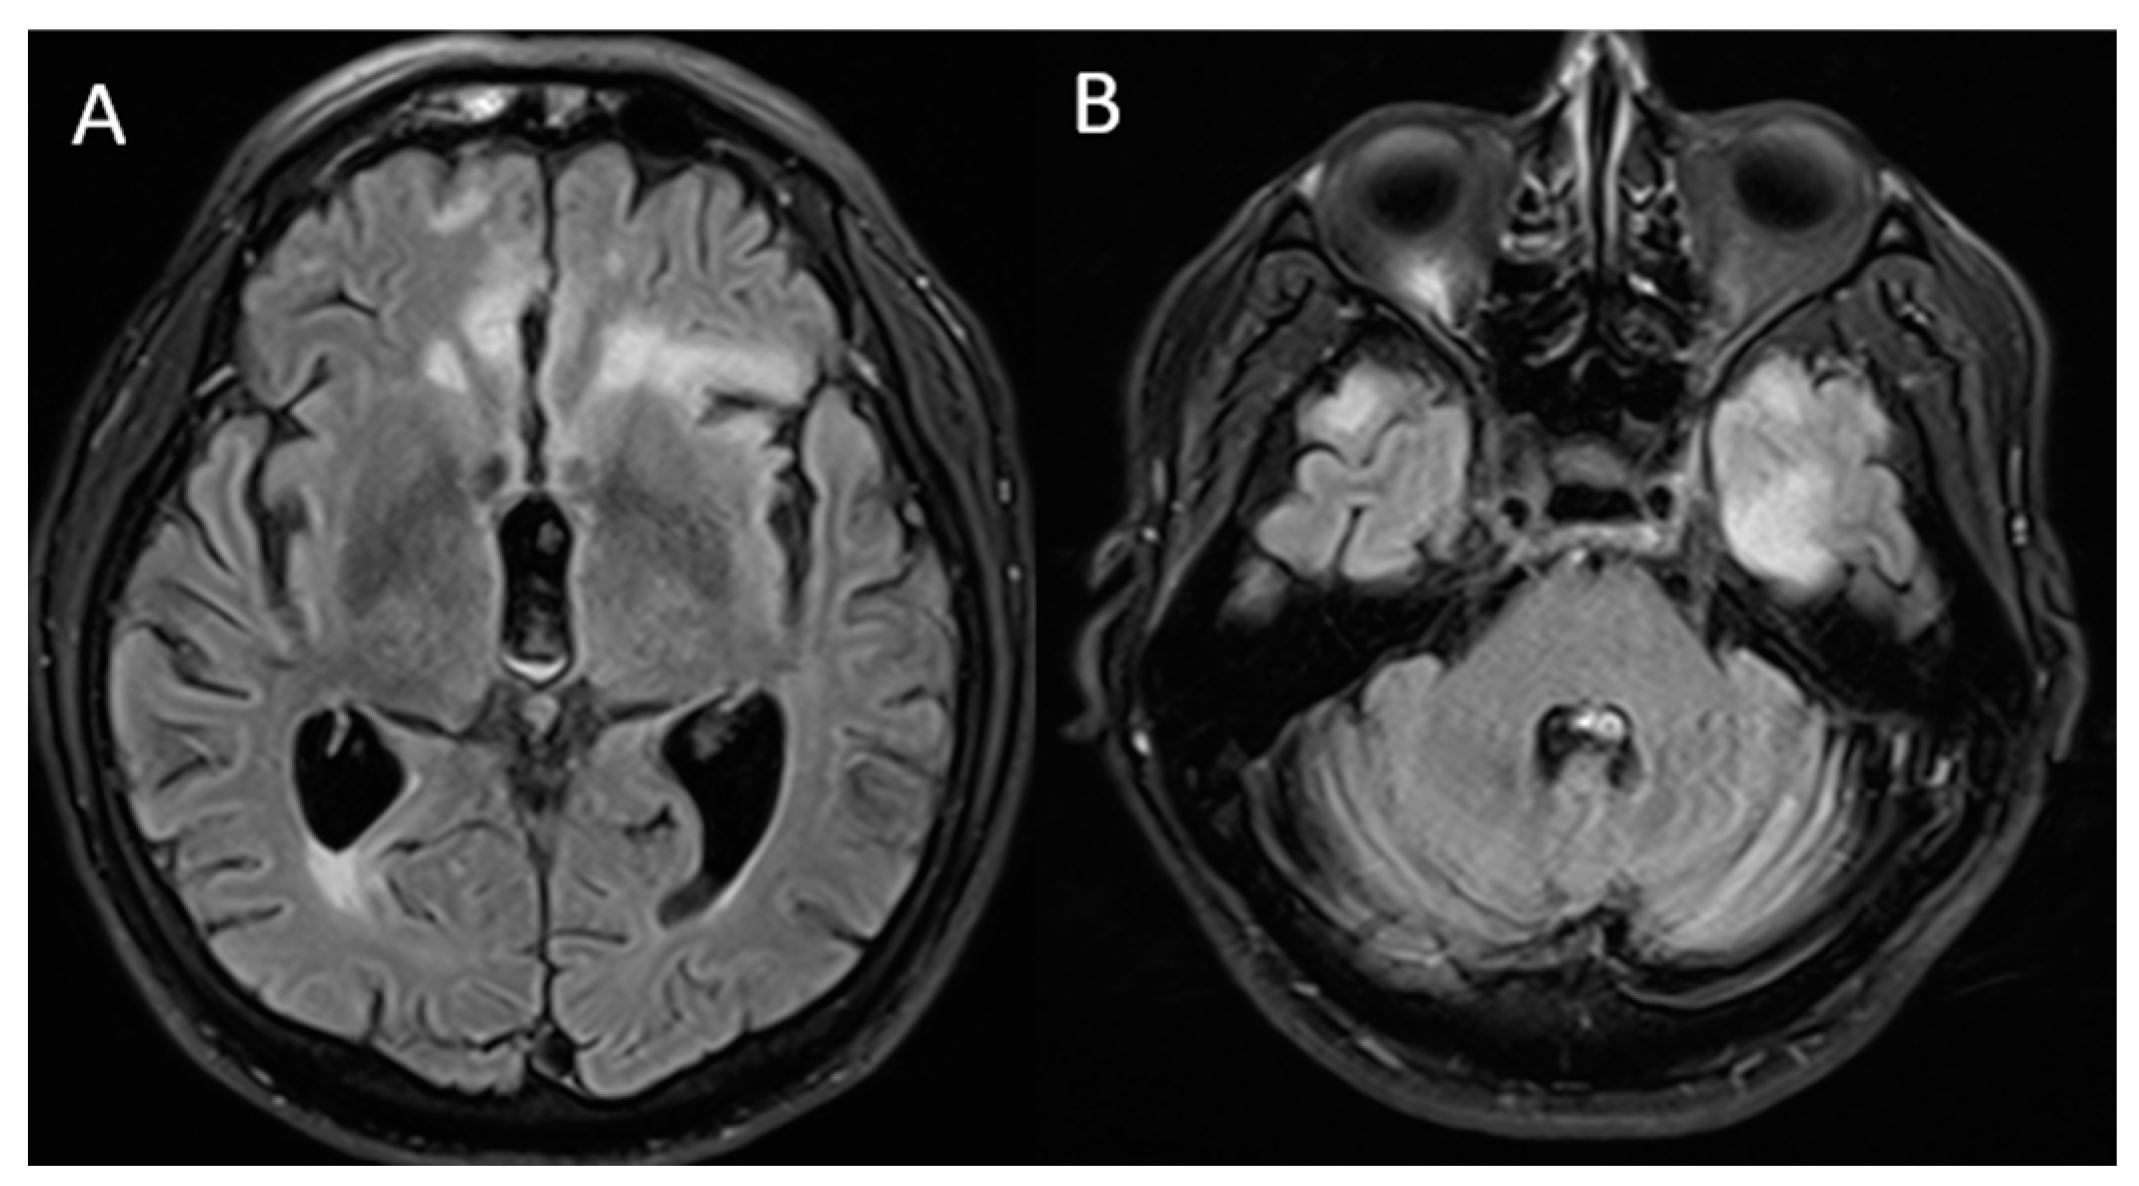

The patient was evaluated by a neurologist who requested new brain MRI, evidencing sequelae lesions at the frontal level, but with aggregation of new demyelinating lesions at the left temporal level (Figure 2). We performed serum tests and a lumbar puncture for suspicion of acute autoimmune encephalopathy (after ruling out a possible infectious process), finding proteinorrhachia (80 mg/dL). We started a five-day immunosuppressive treatment scheme with methylprednisolone at a dose of 1 g daily and immunoglobulin 0.4 g/kg daily.

Figure 2.

Brain magnetic resonance imaging: T2/FLAIR sequence finding (A) lower-volume lesions in the bilateral frontal lobes compared to that in the previous MRI and (B) new hyperintense lesions, predominantly in the left temporal region.

Regarding brain MRI, in most of the previous cases, an image without alterations was presented [6,9,11,12,13], however, one case reported hyperintense images with edema at the hippocampal level [15]. On the other hand, in our case we found hyperintense lesions almost symmetrically. Concerning treatment, in most of the previous reports, methylprednisolone pulses were offered as the first treatment option, obtaining significant clinical improvement [6,9,11,12,14,15], as in our case.